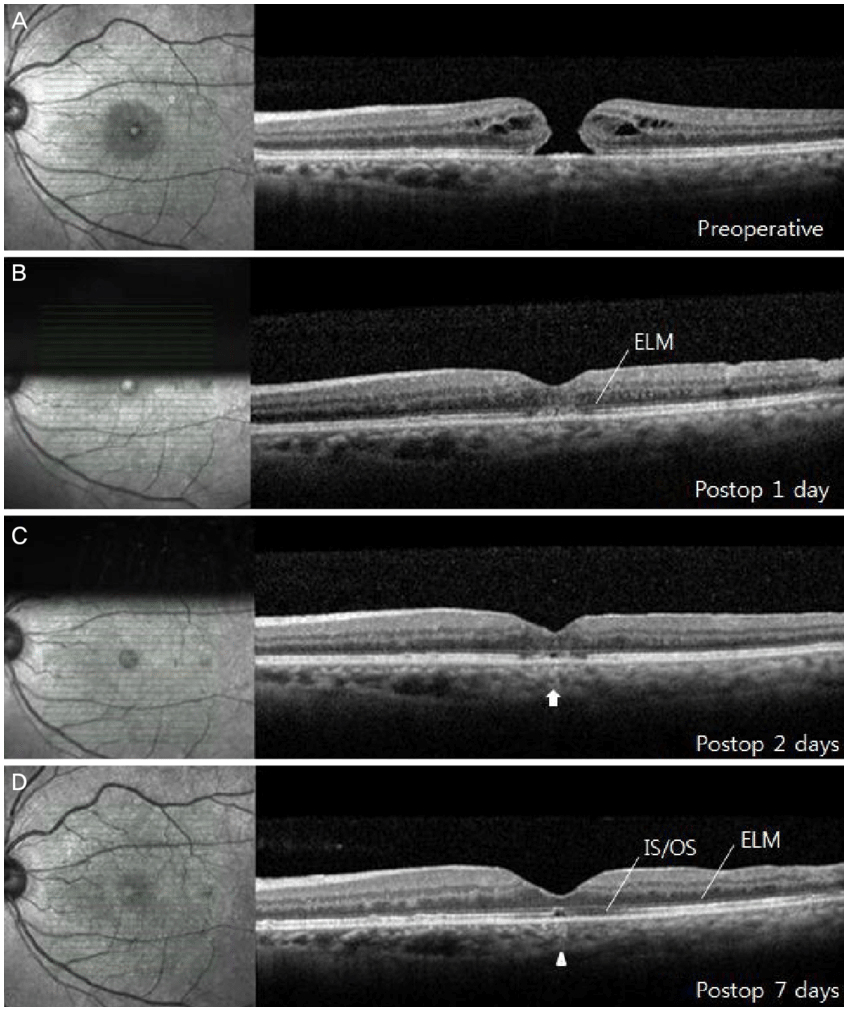

La exploración oftalmológica hace posible establecer el diagnóstico. Existe una prueba denominada tomografía de coherencia óptica (OTC) que permite obtener imágenes de gran precisión, mediante las cuales se puede averiguar el grosor de la retina, la presencia de agujero macular y su grado de evolución.

En determinados casos se han obtenido mejoras de la agudeza visual mediante una intervención quirúrgica denominada vitrectomía, la cual no está exenta de riesgos. Se suelen obtener mejores resultados en los agujeros que han estado presentes un tiempo inferior a 6 meses.[1]